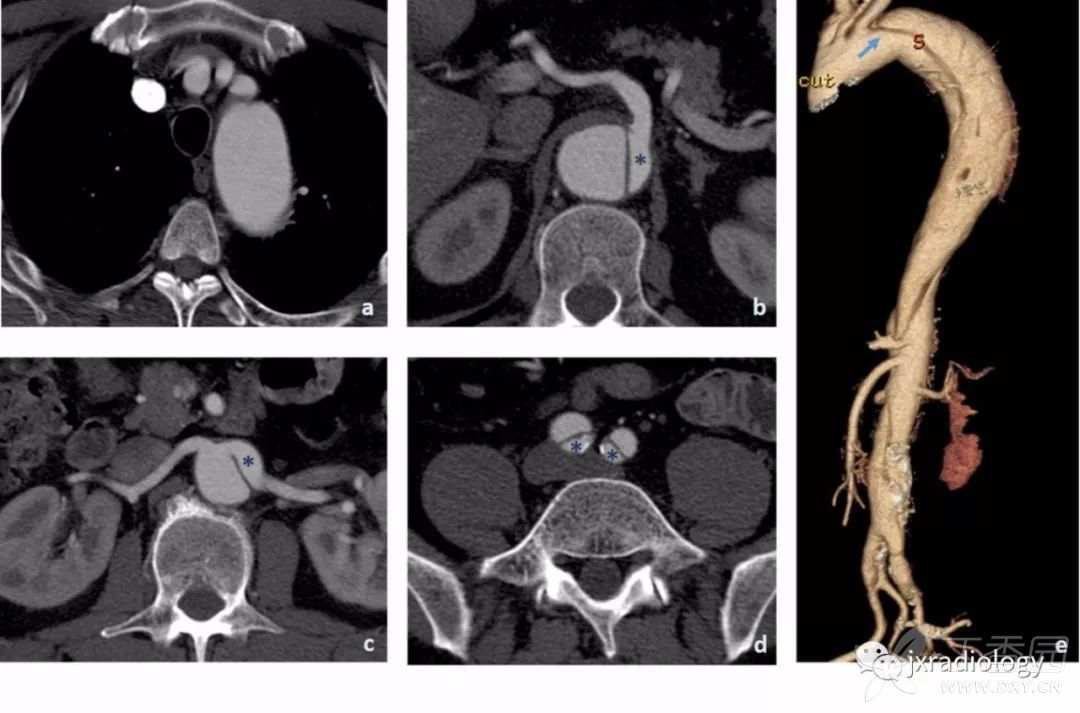

主动脉夹层扩展至主动脉弓上分支不常见(约5-10%),但应提示,因为它可导致脑缺血( 图17 )。

图17:CT示升主动脉中的内膜瓣(a和b图箭头)延伸至降主动脉。内膜瓣延伸到头臂动脉,可见血栓形成(c图箭头显示头臂动脉中的血栓,d图显示颈动脉血栓形成的征象 - 星号显示左颈动脉中,而右颈动脉未见显示)。